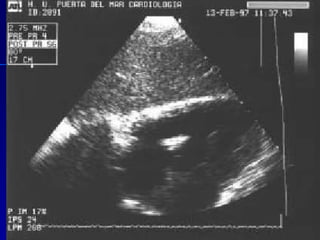

Evidencia de daño miocárdico:   A. ECO positivo para Endocarditis:   (1) Masa intracardiaca móvil,    (2) Abscesos    (3) Prótesis disfuncionante  B.  Insuficiencia valvular nueva

Evidencia de dañomiocárdico: A. ECO positivo para Endocarditis: (1) Masa intracardiaca móvil, (2) Abscesos (3) Prótesis disfuncionante B. Insuficiencia valvular nueva